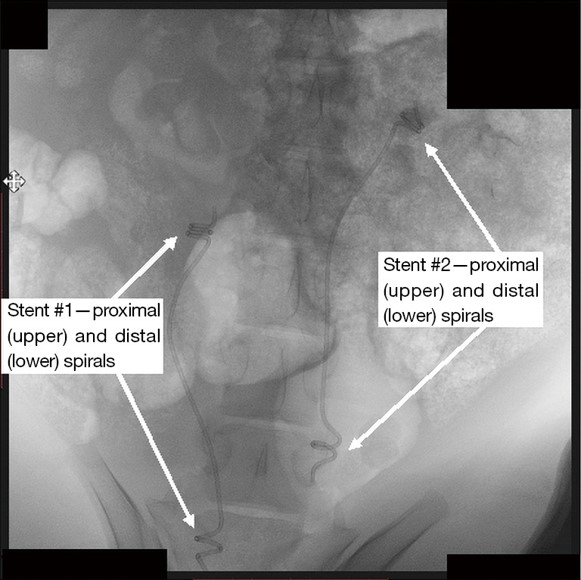

Prototype “YotiCurl” stents emplaced in vivo in a pig model

Prototype stents have been synthesized and successfully tested in a live pig model, demonstrating safe emplacement, full functionality, no stent migration, absence of inflammation, and favorable histological outcomes.